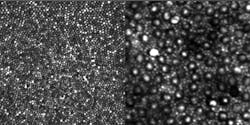

In the eye, the light-sensitive cells known as cones are concentrated at the center of the retina in the fovea centralis; they provide high visual resolution and color vision. Rods are much more numerous than cones, are more sensitive to light, and exist mainly in locations other than the fovea. The rods, which are monochrome sensors and are used in low-light vision, have previously been difficult to image clearly, even with the use of AO.

Reflectance images of a human eye were taken with a 27-year-old male emmetrope (someone with excellent vision without glasses) as the subject. The sinusoidal scan data was made linear by estimating the distortion from images of a Ronchi ruling and then resampling the data. The photoreceptor images can be displayed using a linear grayscale versus image intensity (see figure), or using a logarithmic grayscale mapping, which could be more useful for OCT.